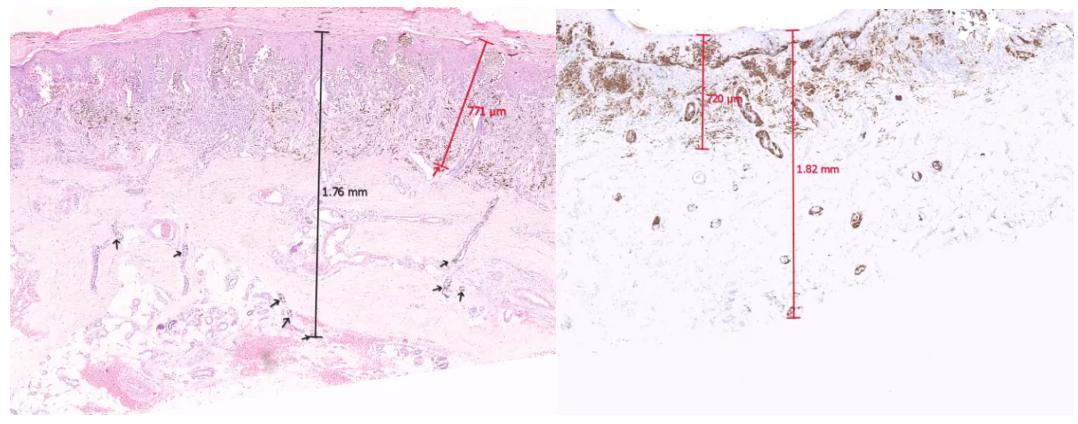

图为不同标准下的不同测量结果

黑色素瘤累及汗腺时,其不同标准下的测量结果容易影响疾病的分期。若按AJCC第8版所示,患者不需进行前哨淋巴结活检;但是,若按照汗腺深度进行测量,则患者应当进行前哨淋巴结活检。AJCC指南提到,应在病理报告中体现累及汗腺的深度,这一点需要我们在临床工作*特中**别注意。